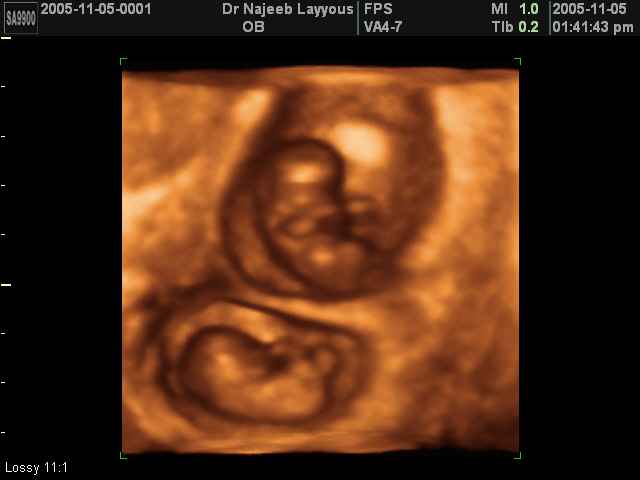

3D Photos échographie de grossesse multiple : Jumeaux, triplés et quadruples| Dr N Layyous

3D Photos échographie de grossesse multiple